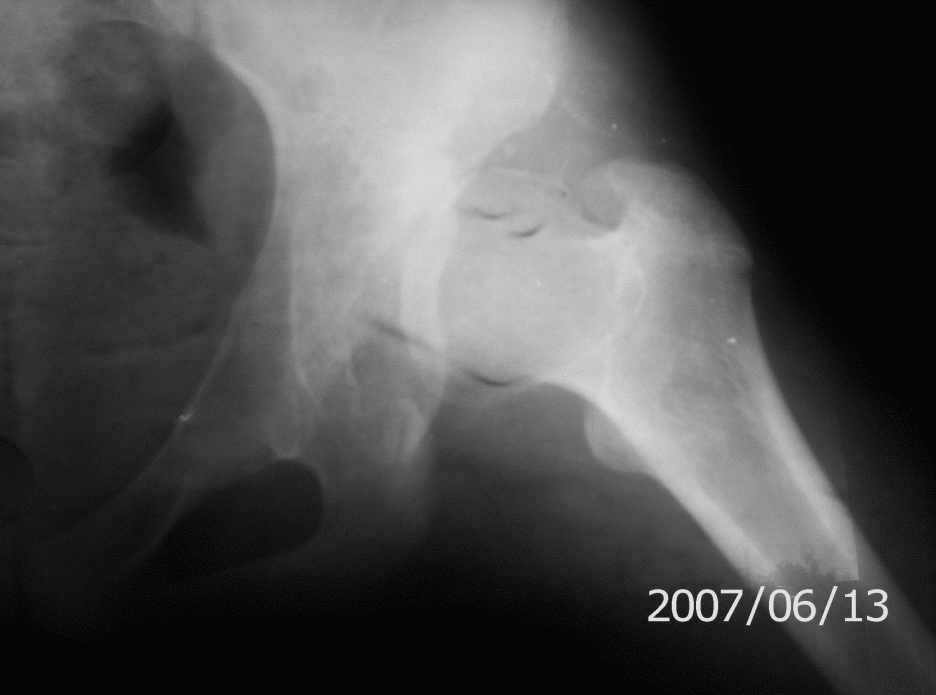

Обратилась девушка 14-ти лет с жалобами на боли в левом тазобедренном суставе,хромоту.

Лечилась консервативно по поводу врожденного вывиха бедра слева.

Движения в суставе не ограничены, укорочение левой н/конечности на1.5 см.